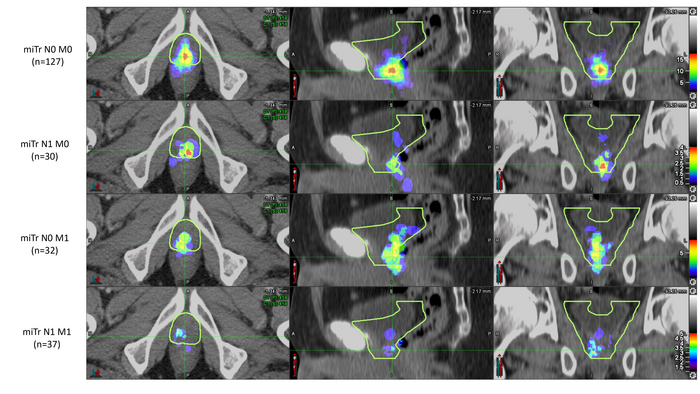

Prostate cancer patients who experienced biochemical recurrence after radical prostatectomy were included in the analysis if their PSMA PET/CT imaging showed recurrence in the prostate bed. To analyze the patterns of recurrence, two nuclear medicine physicians documented the areas of recurrence on the PSMA PET/CT, and four radiation oncologists (masked to the PSMA PET/CT findings) delineated the clinical target volume using RTOG guidelines on the CT images of the PET/CT. PSMA recurrence locations were then compared to the RTOG-based clinical target volumes.

PSMA recurrences were fully covered by the clinical target volumes in 54 percent of the patients. In 34 percent of the patients, PSMA recurrence was only partly covered, and in 13 percent of patients the PSMA recurrence was located fully outside of the clinical target volume.